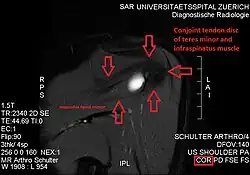

Atrophy of the teres minor muscle is often a consequence of a rotator cuff tear, but common isolated teres minor atrophies have also been found. A quadrangular space syndrome causes excessive and or chronically compression of the structures which pass through this anatomical tunnel. The axillary nerve and the posterior humeral circumflex artery pass through the space. People affected note shoulder pain and paresthesia down the arm first and foremost in abduction, extension, external rotation and overhead activity. Selective atrophy of the teres minor muscle has been seen and pulled together directly with compression of the corresponding axillary nerve branch or posterior humeral circumflex artery. Fibrous bands, cysts of the glenoid labrum, lipoma or dilated veins can occupy the quadrilateral space pathologically. Similar symptoms are common with anterior shoulder dislocation, humeral neck fracture, brachial plexus injury and thoracic outlet and inlet syndrome. It is important to include those pathologies for a complete as possible differential diagnosis.

Ultrasonography is a tool to detect a fatty degenerative atrophy of the teres minor and shows in affected muscles increased echogenicity and betimes a slight reduction in muscle bulk. MR imaging helps to consolidate the diagnosis of neurogenic muscle atrophy. Extracellular edema after traumatic events causing neural damage show an increased signal intensity on T2-weighted MRI sequences and normal intensity on T1-weighted sequences. Posterior humeral circumflex artery compression and reduced blood flow in stressful arm positions and or maneuvers can be diagnosed by a Doppler ultrasonography. The nerve should be detected adjacent to the vessel. In an elevated arm position the axillary neurovascular bundle can be seen at the posterior axillary fold just before it perforates the deltoideus, while the posterior course is well visible in the neutral position. For a detailed assessment of the artery, a MR angiography is required. The major task of an ultrasonographic examination is to rule out any space occupying mass. Additional electromyography is helpful to reveal any decelerated nerve conduction velocity, and thus denervation of the concerned muscle.[6]